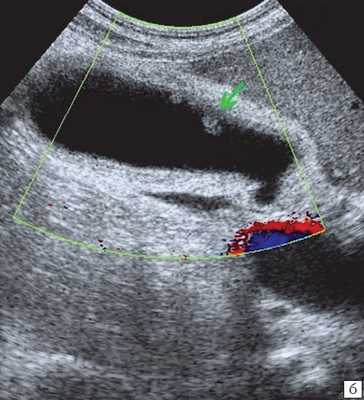

- Ультразвуковая диагностика. К визуализирующим методам диагностики холангита относятся УЗИ брюшной полости и печени, ультрасонография желчных путей. С их помощью удается получить изображение желчных протоков, выявить их расширение, определить наличие структурных и очаговых изменений в печени.

Ультрасонография является эффективным средством выявления полиповидной формы холестероза 8. Традиционной считается следующая сонографическая характеристика холестериновых полипов: неподвижные гиперэхогенные структуры, которые не дают акустической тени и прикрепляются к стенке желчного пузыря. Контуры таких образований, как правило, ровные, а размеры таких образований различны, чаще не превышают 10 мм (рис. 2).

При распространенном холестерозе визуализируются множественные гиперэхогенные образования, дающие картину "земляничного" желчного пузыря (рис. 3).

а) Множественные полипы в желчном пузыре, картина "земляничного" желчного пузыря.

б) В режиме цветного допплеровского картирования кровоток не регистрируется.